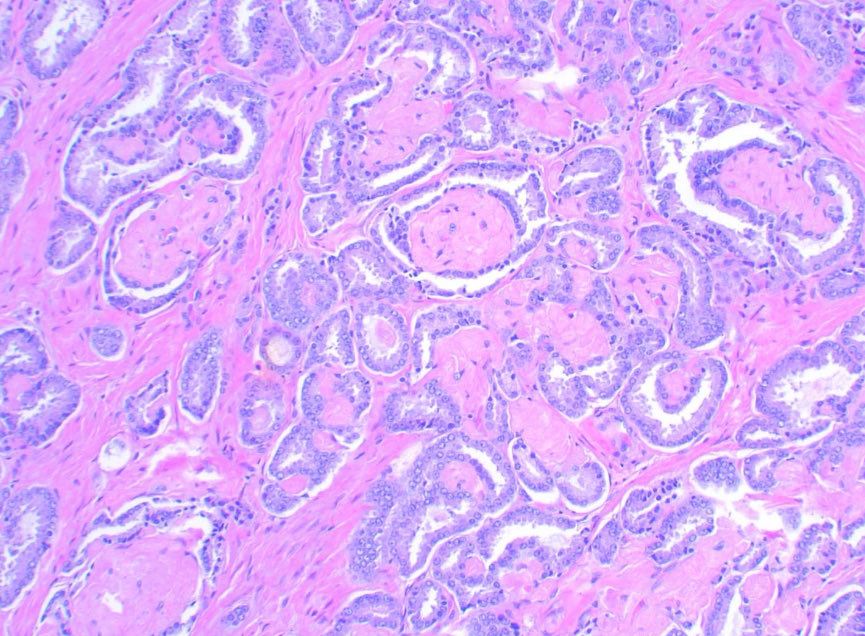

A bona fide GP 3 prostatic carcinoma: well formed discrete 👌🏽 See why you shouldn’t grade PNI? 🤓 #GUpath #PathX #Pathology #PathTwitter